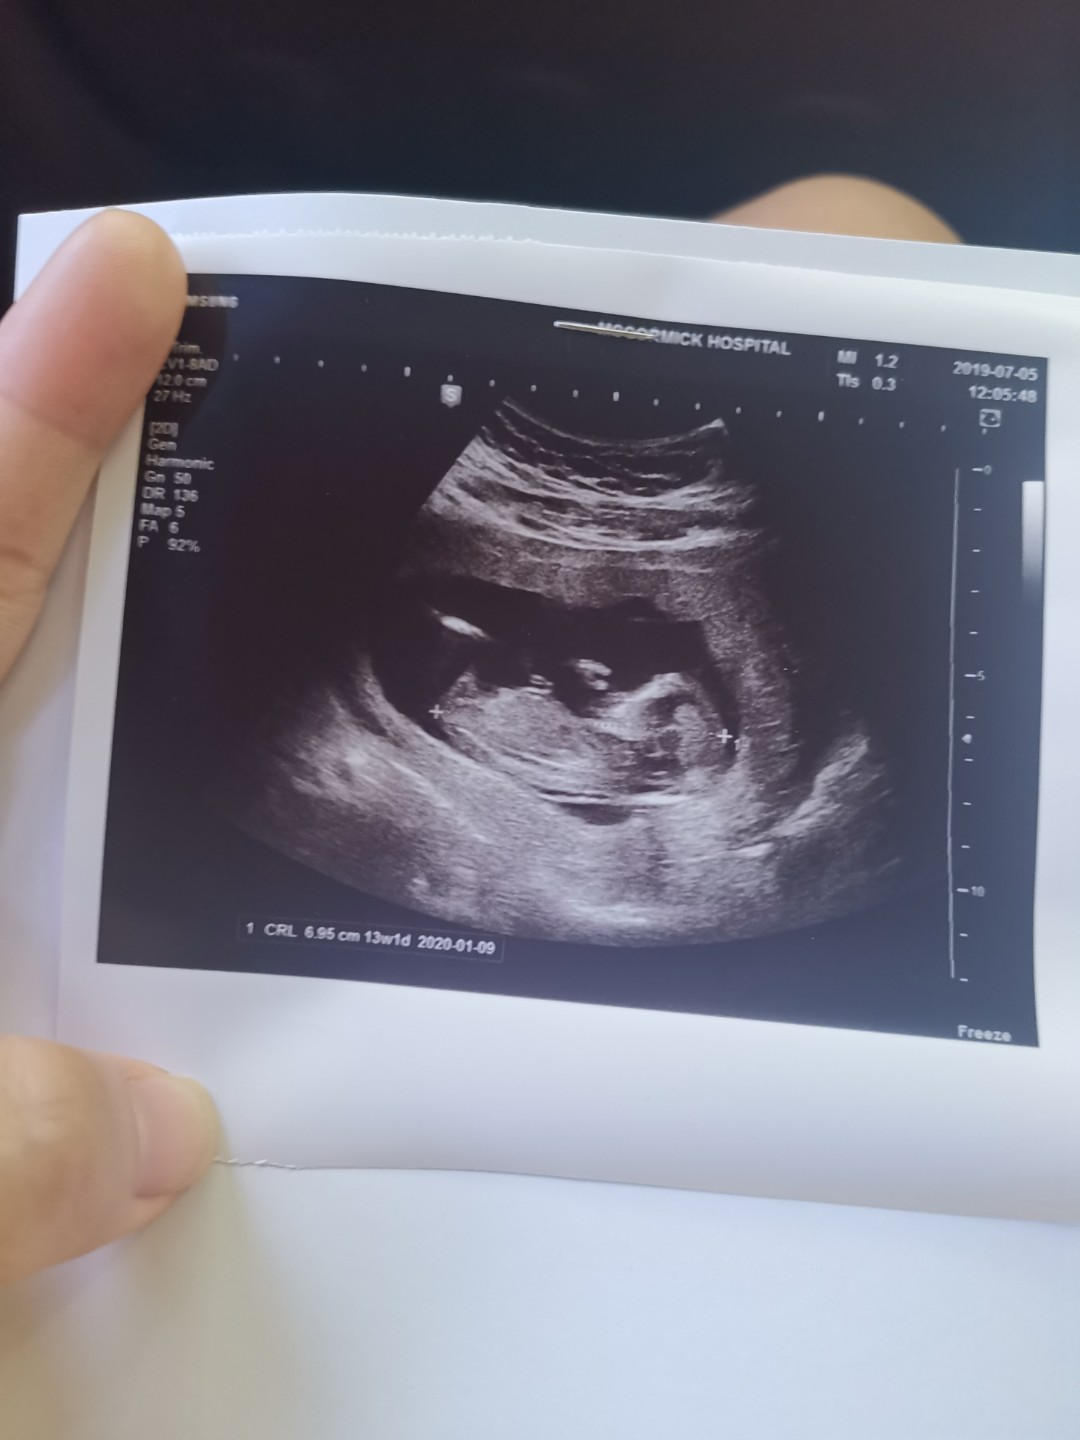

14wค่ะ